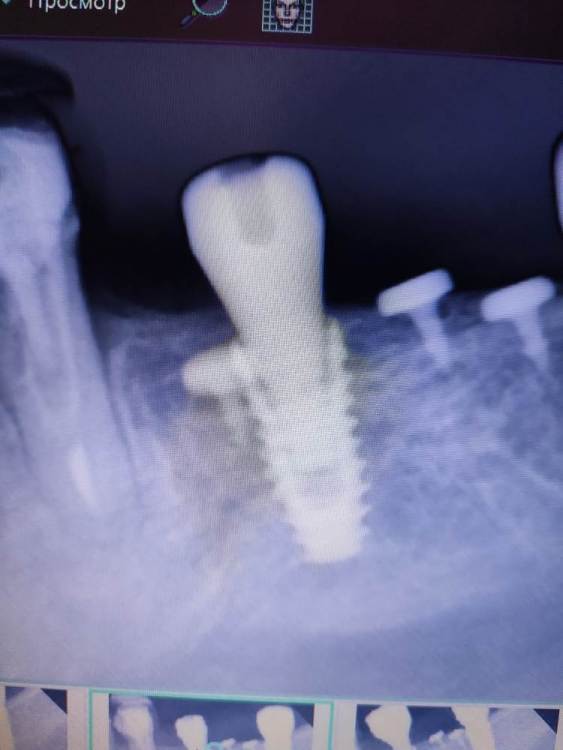

АнтонТЛТ Опубликовано 22 октября, 2022 Поделиться Опубликовано 22 октября, 2022 11 минут назад, kriokov сказал: не смог нормально поставить ФДМ на необиотек 3. 5 и 4.0. ФДМ от дентиума. Кость не мешала, убирал римерами. Шахта чистая. Какая причина может быть? Снимок не делали? Ссылка на комментарий

kriokov Опубликовано 22 октября, 2022 Поделиться Опубликовано 22 октября, 2022 6.5 , только на такую глубину, далее 5.5 тоже не сел, потом от мис поставил, . По снимкам кажется что кость . На самом деле полно места. Не пойму, что не так сделал. Ссылка на комментарий

АнтонТЛТ Опубликовано 22 октября, 2022 Поделиться Опубликовано 22 октября, 2022 42 минуты назад, kriokov сказал: Точно. Еще был под рукой от осстема, я не стал пробовать . От миса сел . К следующему пиему привезут родные. отпишусь. Не понятно почему один и тот же фдм в один болт вошел а в дугой нет. Может быть конусность чуть разная или это домыслы? Домыслы. Может с резьбой что-то у фдм. По рентгену же видно, что до конуса не дошло. 1 Ссылка на комментарий